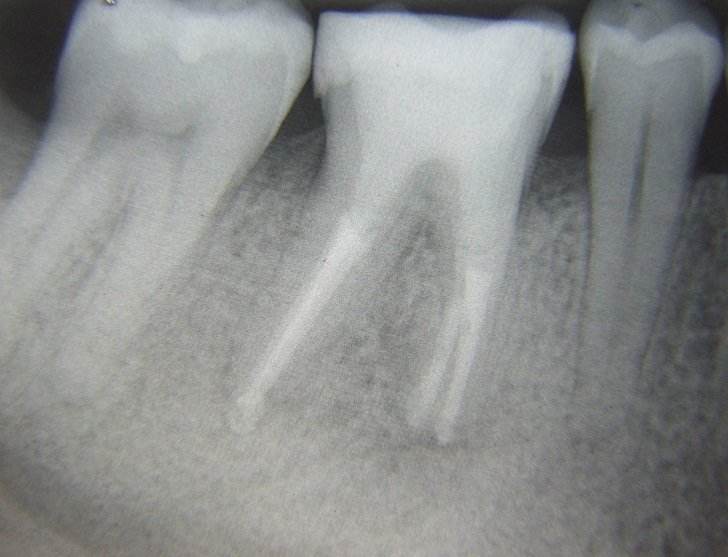

Desi nu este de dorit, uneori se constata prezenta unor leziuni extinse (granuloame, chisturi) care daca nu sunt rezolvate corespunzator, pun in pericol viabilitatatea dintelui.

Din nou tratamentul sub microscop optic efectuat de catre specialistii endodonti poate duce la salvarea dintelui.